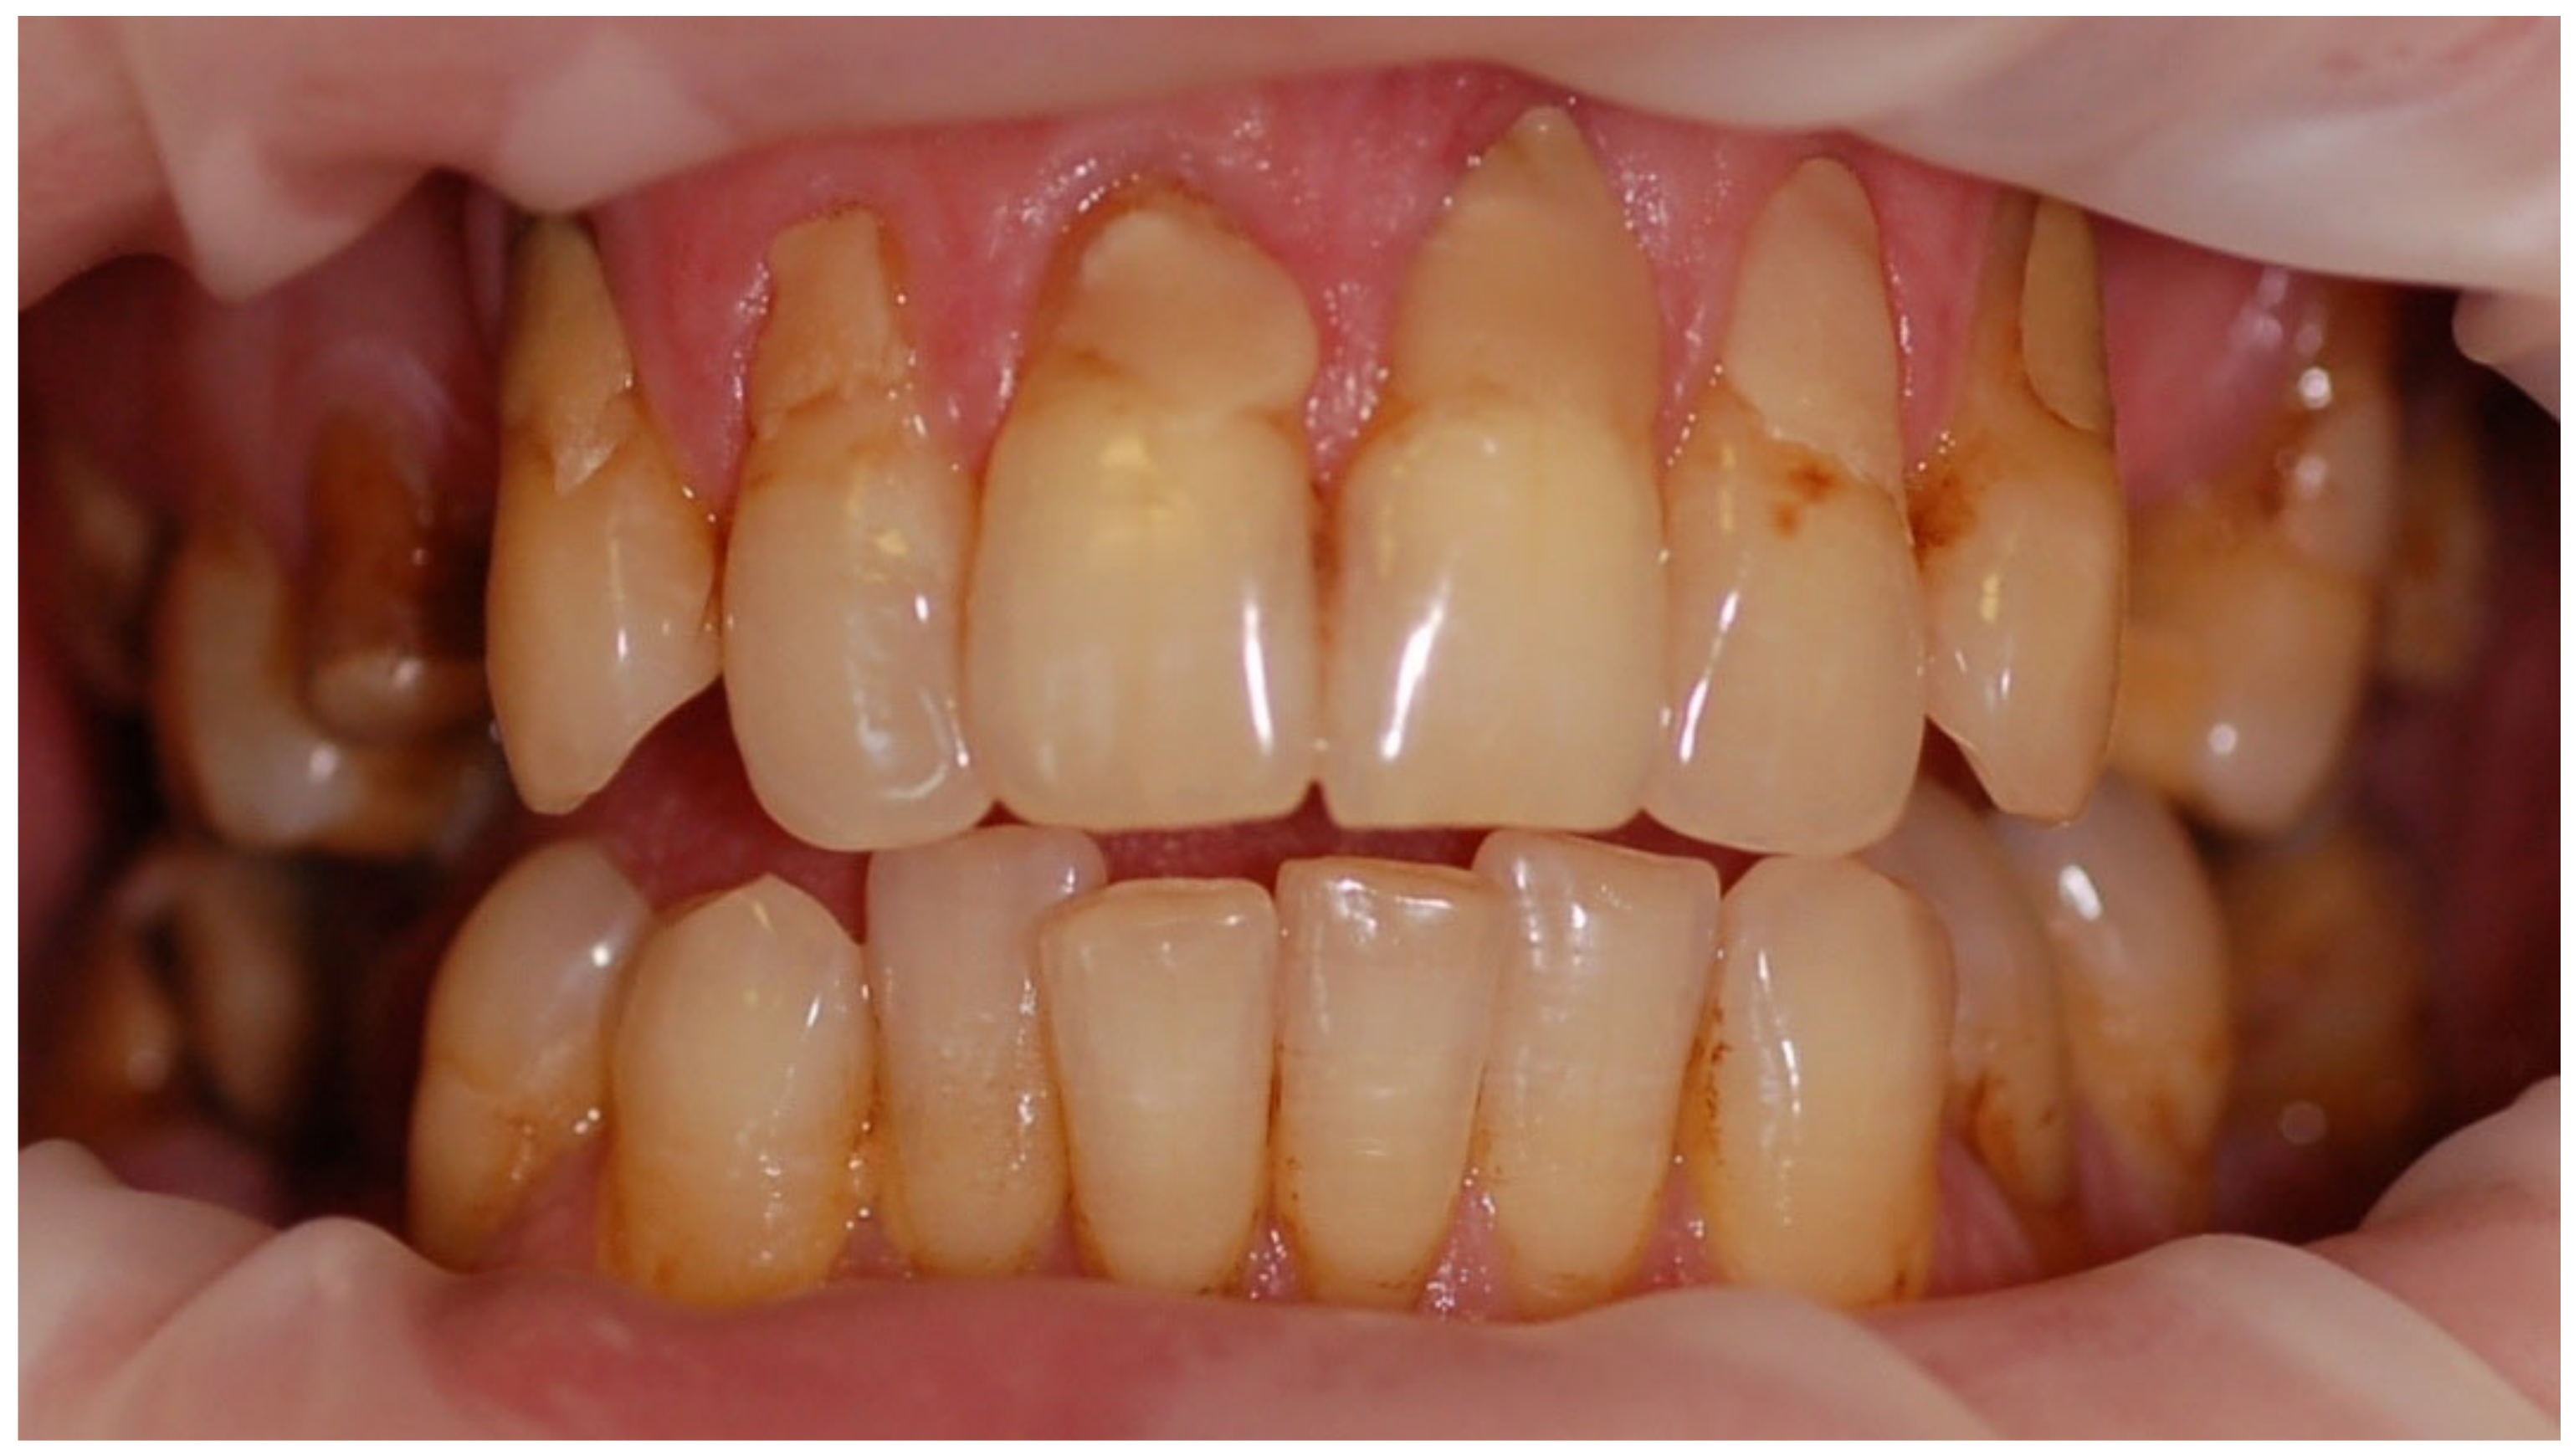

The mean API score among the subjects was 63.47% (SD = 22.78) and ranged between 22 and 100%. The mean value of the index for the control group was 68.75% (SD 21.46) and ranged from 19 to 100%. The p > 0.05, therefore the study and control groups did not differ significantly from the API value. The median value of the API index for the study group was 65 and 68.5 for the control group. Table 3 and Figure 1 present the API score and the API score pictured according to interpretation values. Figure 2, Figure 3 and Figure 4 show the clinical situation of the participants. The API values did not have a normal distribution in the analyzed groups (p < 0.05 from the Shapiro–Wilk test), so the analysis was carried out using the Mann–Whitney test.

Figure 2. Woman, 23 y.o. Clinical situation, API = 100%. Dental Biofilm-induced Gingivitis. Leaking restorations.

Ijerph 20 04792 g002

Figure 3. Man, 28 y.o. API = 100%. Calculus and dental plaque deposits. Dental Biofilm-induced Gingivitis. Teeth discoloration and superficial caries lesions.

Ijerph 20 04792 g003